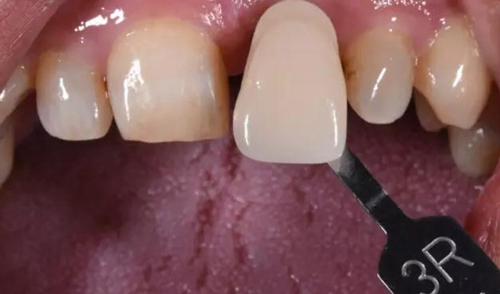

病例1:C先生,36歲,門牙外傷后拔除后3月。就診要求修復(fù)。

缺牙區(qū)比色照